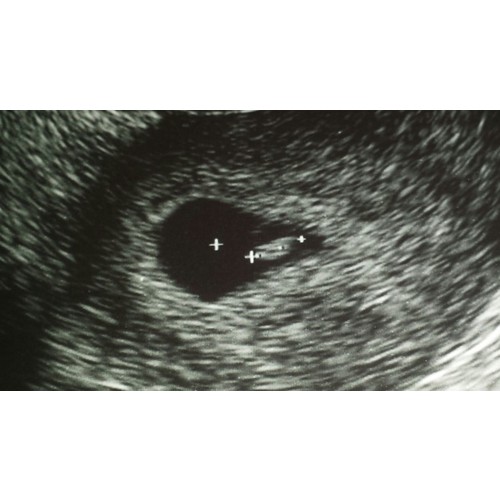

Ik heb ietsje eerder dan 6 weken een inwendige echo gehad in het ziekenhuis ivm eerdere miskramen. De gynaecoloog gaf aan dat ik ongeveer 5 weken en een beetje was. En het allermooiste was dat we het hartje zagen kloppen ❤️! En het vruchtje was ongeveer 3.66 mm. Maandag mag ik weer langskomen, dan ben ik exact twee weken verder.

5+6 kloppend hartje toen ook gezien helaas met 7 weken een miskraam 😢 maar hoop dat je aan de echo zelf iets heb 😘